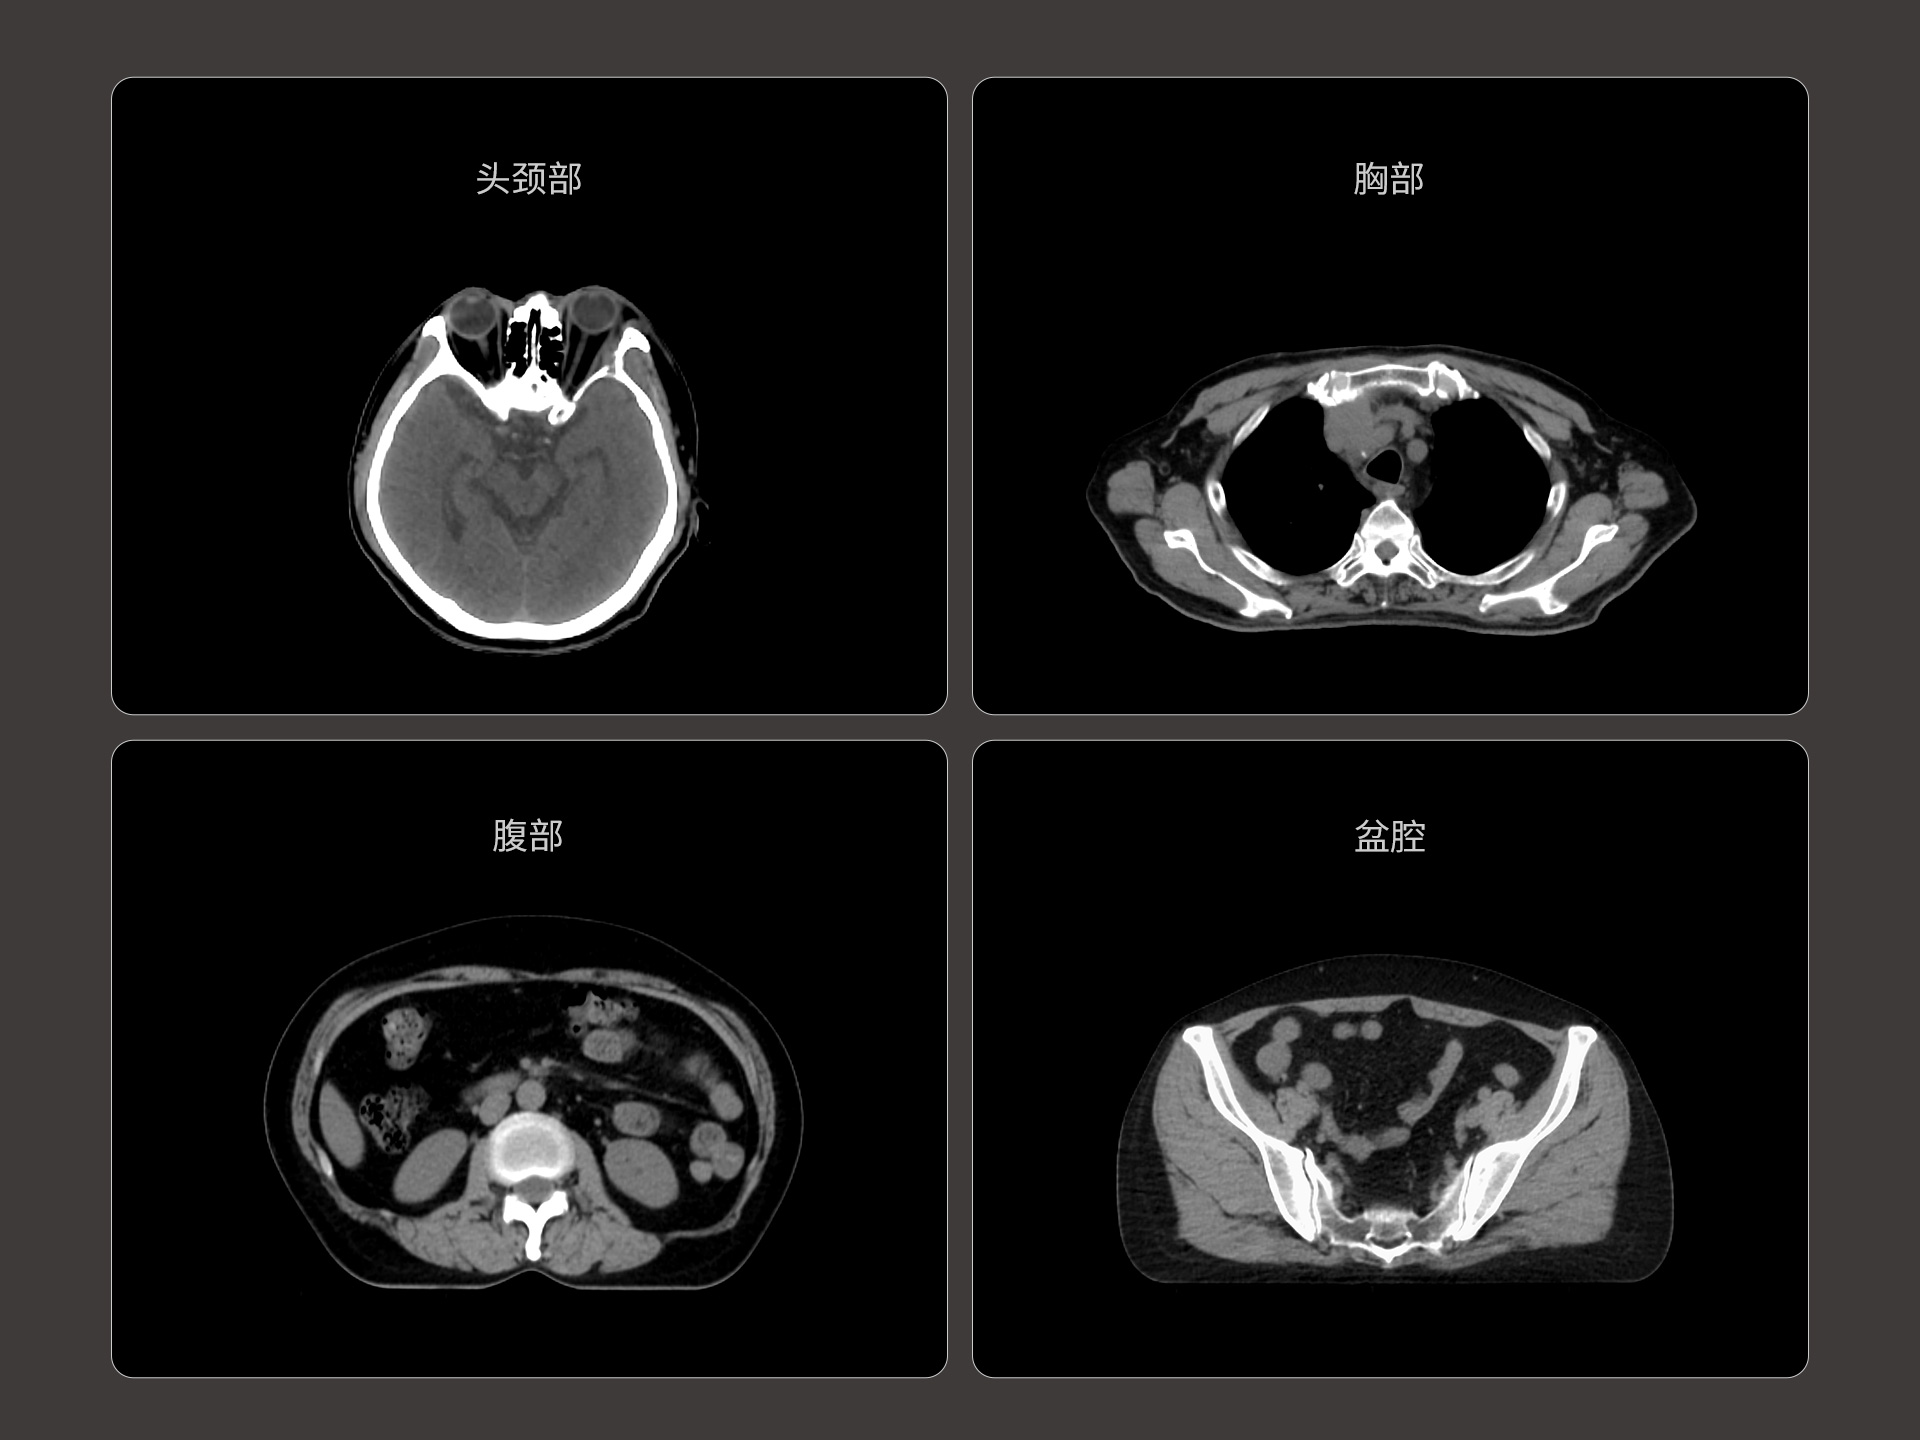

uLinac HalosTx®搭载新一代 87cm 大孔径诊断级CT图像引导系统,全能进阶,实现高清图像质量和全景视野的完美平衡,开辟全疗程 「影像感知」 ,为临床提供更自信、更全面的临床依据。

扇形束成像,极低散射,媲美CT-sim的影像品质3mm @ 0.3% 高软组织对比度,0.55mm薄层扫描,精确鉴别肿瘤靶区边界全疗程肿瘤变化感知,加速高清影像引导高水平普及

精准CT值,完美满足勾画、剂量计算要求从数据源头提升图像质量,高清呈现细微变化,全面精进机载影像实力提供传统 的CT 模拟机所一致的HU值精度(±10HU)

87cm CT影像孔径设计适配多种摆位姿势,兼顾不同体型患者标准视野 63cm,避免扫描信息缺失轴向视野 91cm,轻松实现长靶区扫描

0.37s/360° 旋转速度,减少运动伪影,大幅提高时间分辨率4D CT 动态肿瘤追踪,运动靶区精准勾画低剂量CT,保证成像质量的同时降低患者辐射剂量